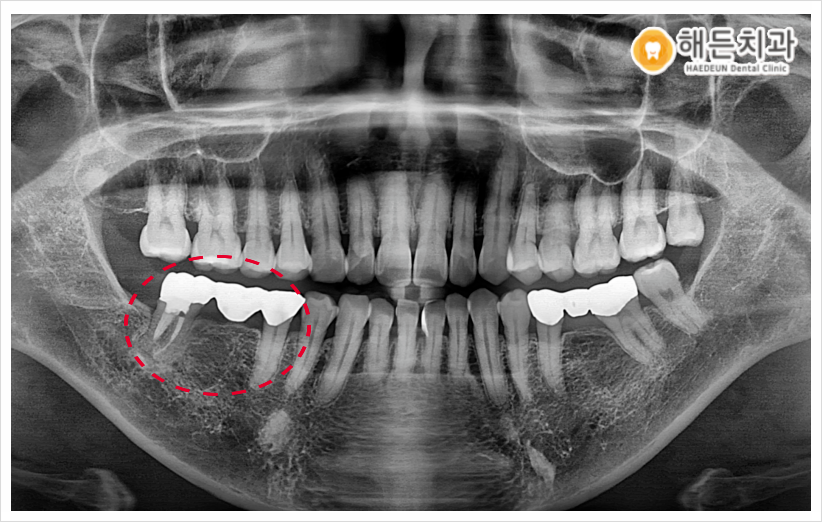

오른쪽 밑에 브릿지 크라운을 확인해 보니

브릿지 크라운이 씌워져 있던

치아의 잇몸도 꽤 내려가 있었고

그 틈 사이로 음식물이 끼면서 관리가 잘 안되어,

잇몸이 자주 붓고

불편하셨다고 말씀해주셨습니다.(ㅠㅠ)

지금도 잇몸뼈가 일부 녹아 내려간 상태라

그대로 둘 경우 머지않아

치아 흔들림, 통증 등 불편감이 생길 수 있어

기존 브릿지 크라운을 제거 후

가운데 빈자리에는 임플란트를 식립하고,

양옆의 치아에는

크라운을 따로 하나씩

씌워 주기로 결정하였습니다.